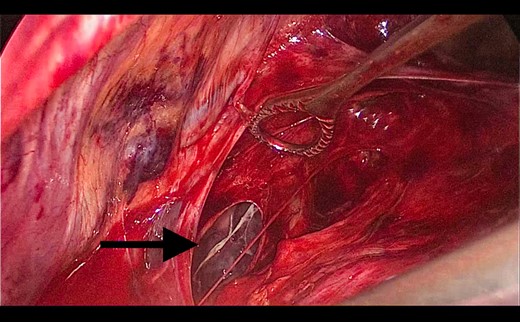

A 73-year-old male patient with a clinical history of COPD, lung emphysema and a 30-year smoking history was admitted to the ED due to a 24-h clinical picture of dyspnea immediately following a sudden bout of dry coughing. Physical examination showed a dyspneic patient, tachypnea of 25 rpm, heart rate of 85 bpm and blood Pressure of 135/75 mmHg along with central cyanosis. Chest exam showed a hyper-resonant right hemithorax along with reduced breath sounds. Initial chest X-ray revealed a large right-sided pneumothorax (Fig. 1). A right chest tube was placed in the ED. Emergency echocardiogram had no significant findings and spirometry showed suspected patterns of obstruction. Following patient stabilization, a high-resolution chest computed tomography (HRCT) was performed revealing extensive pan lobar emphysema throughout both lungs, para septal emphysema in both the anterior upper lobes and herniation of a left lung bullae through the anterior mediastinal pleura along with a right-sided pneumothorax with the chest tube in place with persistent air space (Fig. 2). The patient was taken to surgery where a right video-assisted thoracoscopic (VATS) approach showed severe lung emphysema and a contralateral herniated left lung bulla through the mediastinal pleura anterior to the pericardium (Fig. 3). Right pleurodesis was performed using Talc and a left posterior thoracoscopy showed a severe emphysematous left lung with a lingular herniated bulla to the right hemithorax through an anterior mediastinal pleural defect along with pleural adhesions (Figs 4 and 5). Thoracoscopic hernia reduction was performed along with bullectomy using 60 mm mechanical sutures (Fig. 6). Chest tubes were removed on POD 3 (right) and POD 4 (left). The patient had significant respiratory improvement and was discharged on POD 5.

Thoracoscopic view from left side of thoracoscopic bullectomy.